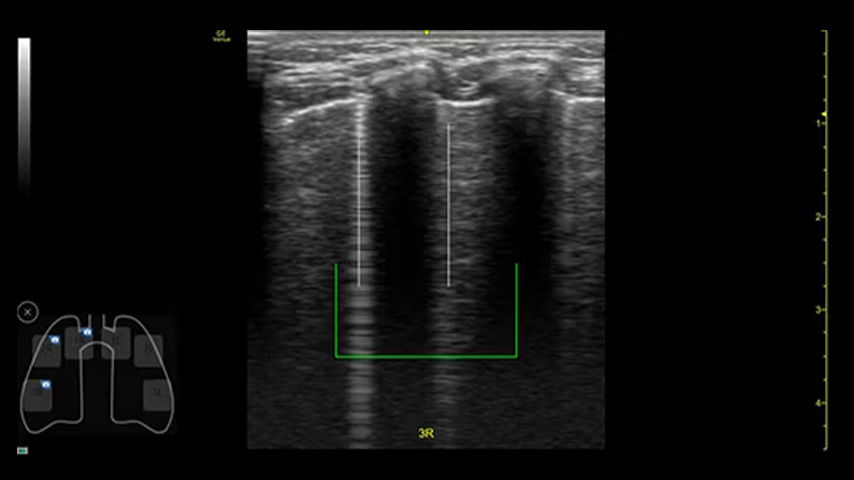

Enhance accuracy

Needle recognition software helps with visualization for line placements